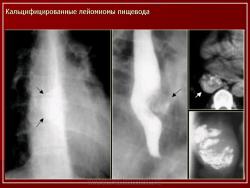

Наблюдения коллег.

Приложения:

51..Slayd55.JPG101.Slayd32.JPG102.Slayd33.JPG